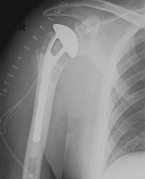

Right: radiograph of an inverse shoulder prosthesis for rotator cuff defect arthropathy.

left: Inverted shoulder prosthesis (Aequalis reversed type, Tornier company).